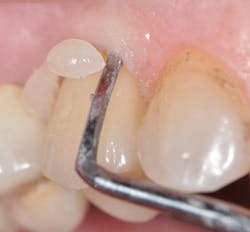

Zirconia can be made a better candidate for bonding when treated with airborne particle abrasion and tribochemical silica coating (Danville's SilJet).6 Lithium disilicate is best pretreated with hydrofluoric acid. Unfortunately, these pretreatment regimens are compromised by saliva after trying them intraorally. Prior to final cementation, I recommend decontaminating the restoration using a product such as Ivoclar's Ivoclean (figure 3). A silanating agent (e.g., Monobond Plus from Ivoclar Vivadent)2 is then placed inside the ceramic restoration (figure 4).

Figure 3: To decontaminate the restoration, rinse, then scrub with Ivoclean, leave for 20 seconds, and rinse.